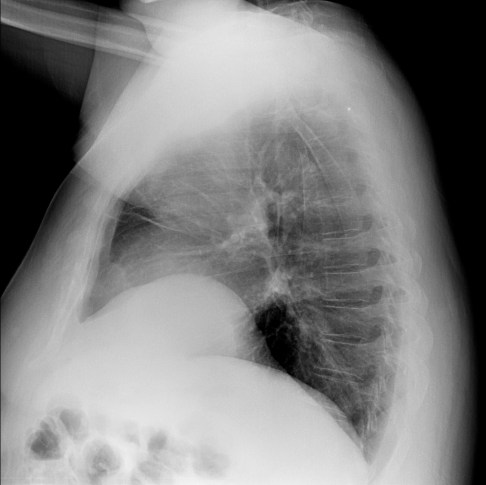

CASO: Febrícula y tos de 4 días de evolución.

Hallazgos:

- En la placa PA se observa una asimetría en los hilios pulmonares, el hilio izquierdo tiene una densidad aumentada.

- Tras examinar la placa lateral se observa un aumento de densidad en la columna que puede ser compatible con una condensación, es el signo de la desnificación vertebral.

SIGNO DE LA DENSIFICACIÓN VERTEBRAL: En la radiografía lateral normal, la densidad de la columna torácica tiende a disminuir desde la parte superior hasta el diafragma; la alteración de ese patrón por la presencia de una densidad superpuesta a la columna, indica la existencia de una consolidación pulmonar. Este signo adquiere especial valor cuando en la proyección posteroanterior la consolidación está oculta en el espacio retrocardíaco o en la base pulmonar.